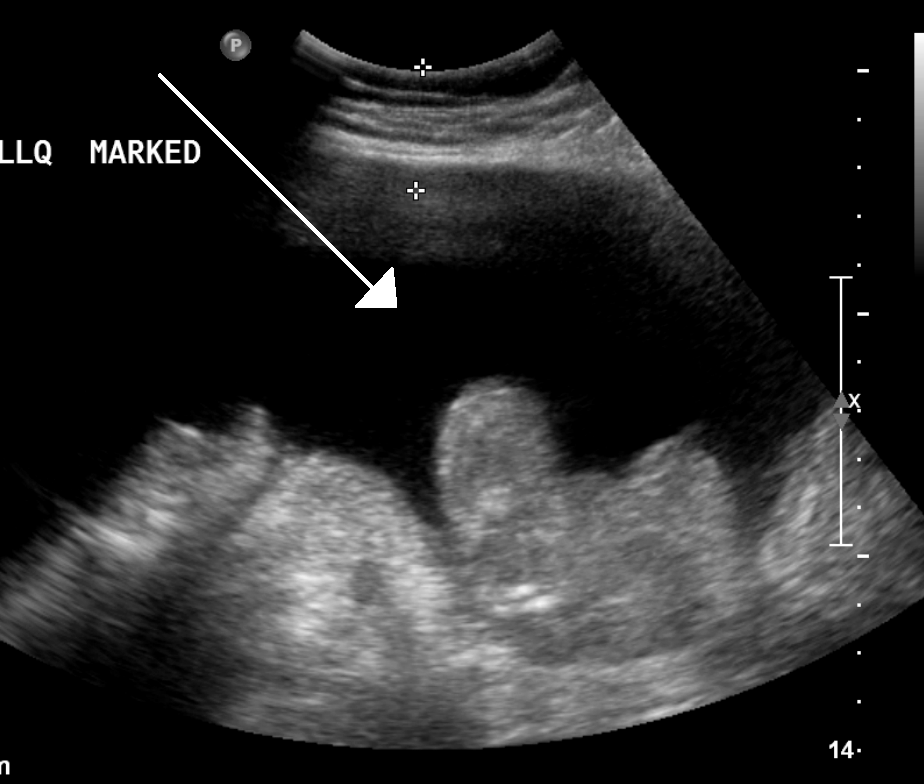

4. 1. 신체 검진

복수의 진단은 신체검진이나 영상의학적 검사를 통해서 할 수 있다. 일반적으로 신체검진 시 타진으로 평가하는 이동탁음(shifting dullness)은 500mL 이상의 복수가 있을 때 진단 가능하며, 초음파 검사는 100mL 이상의 복수가 차 있는 경우 진단 가능하다.

초음파 검사는 100mL 이상의 복수가 차 있는 경우 진단 가능하며, 복부 장기의 크기와 모양을 보여줄 수 있고, 도플러 검사를 통해 문맥의 흐름 방향을 보여주거나 바드-키아리 증후군(간정맥 혈전증) 및 문맥 혈전증을 감지할 수 있다.[13] 초음파 검사자는 복수액의 양을 추정할 수 있으며, 배액이 어려운 복수는 초음파 유도하에 배액할 수 있다. 복부 CT 스캔은 복부 장기 구조와 형태를 파악하는 데 초음파보다 더 정확하다.[13]4. 3. 복수 천자

초음파 검사는 복부에서 체액을 제거하기 전에 자주 시행된다. 이는 복부 장기의 크기와 모양을 보여줄 수 있으며, 도플러 검사를 통해 문맥의 흐름 방향을 보여줄 뿐만 아니라 바드-키아리 증후군 (간정맥 혈전증) 및 문맥 혈전증을 감지할 수 있다. 초음파 검사자는 또한 복수액의 양을 추정할 수 있으며, 배액이 어려운 복수는 초음파 유도하에 배액할 수 있다. 복부 CT 스캔은 복부 장기 구조와 형태를 파악하는 데 초음파보다 더 정확하다.[13]